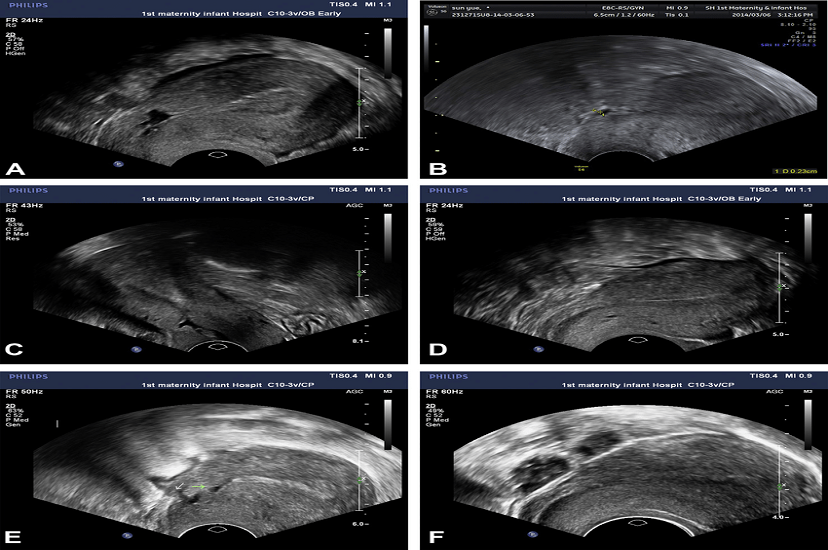

A Doppler ultrasound is a noninvasive test that can be used to estimate the blood flow through your blood vessels by bouncing high-frequency sound waves (ultrasound) off circulating red blood cells. A regular ultrasound uses sound waves to produce images, but can’t show blood flow.

A Doppler ultrasound test may also help your doctor check for injuries to your arteries or to monitor certain treatments to your veins and arteries.